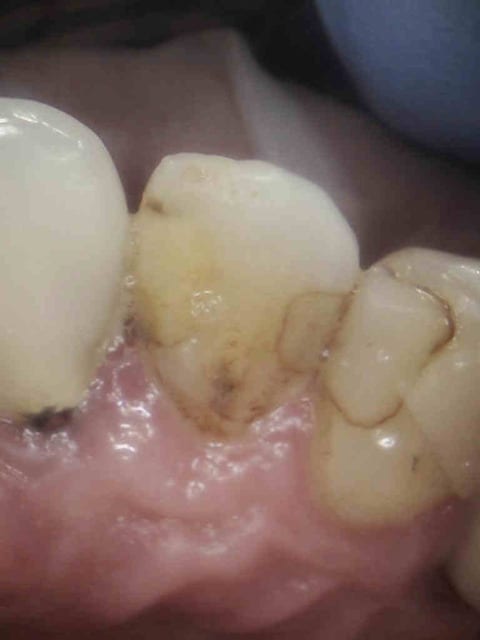

Un peu de Registrans (silicone transparent) et le compo devient facile ;)

Compo  1  tm0ica - Eugenol

Compo  2  sybe5j - Eugenol

Compo  4  mgtloe - Eugenol

Compo  5  gjz0bm - Eugenol

Compo  6  jatise - Eugenol

Compo  7  uj0ux9 - Eugenol